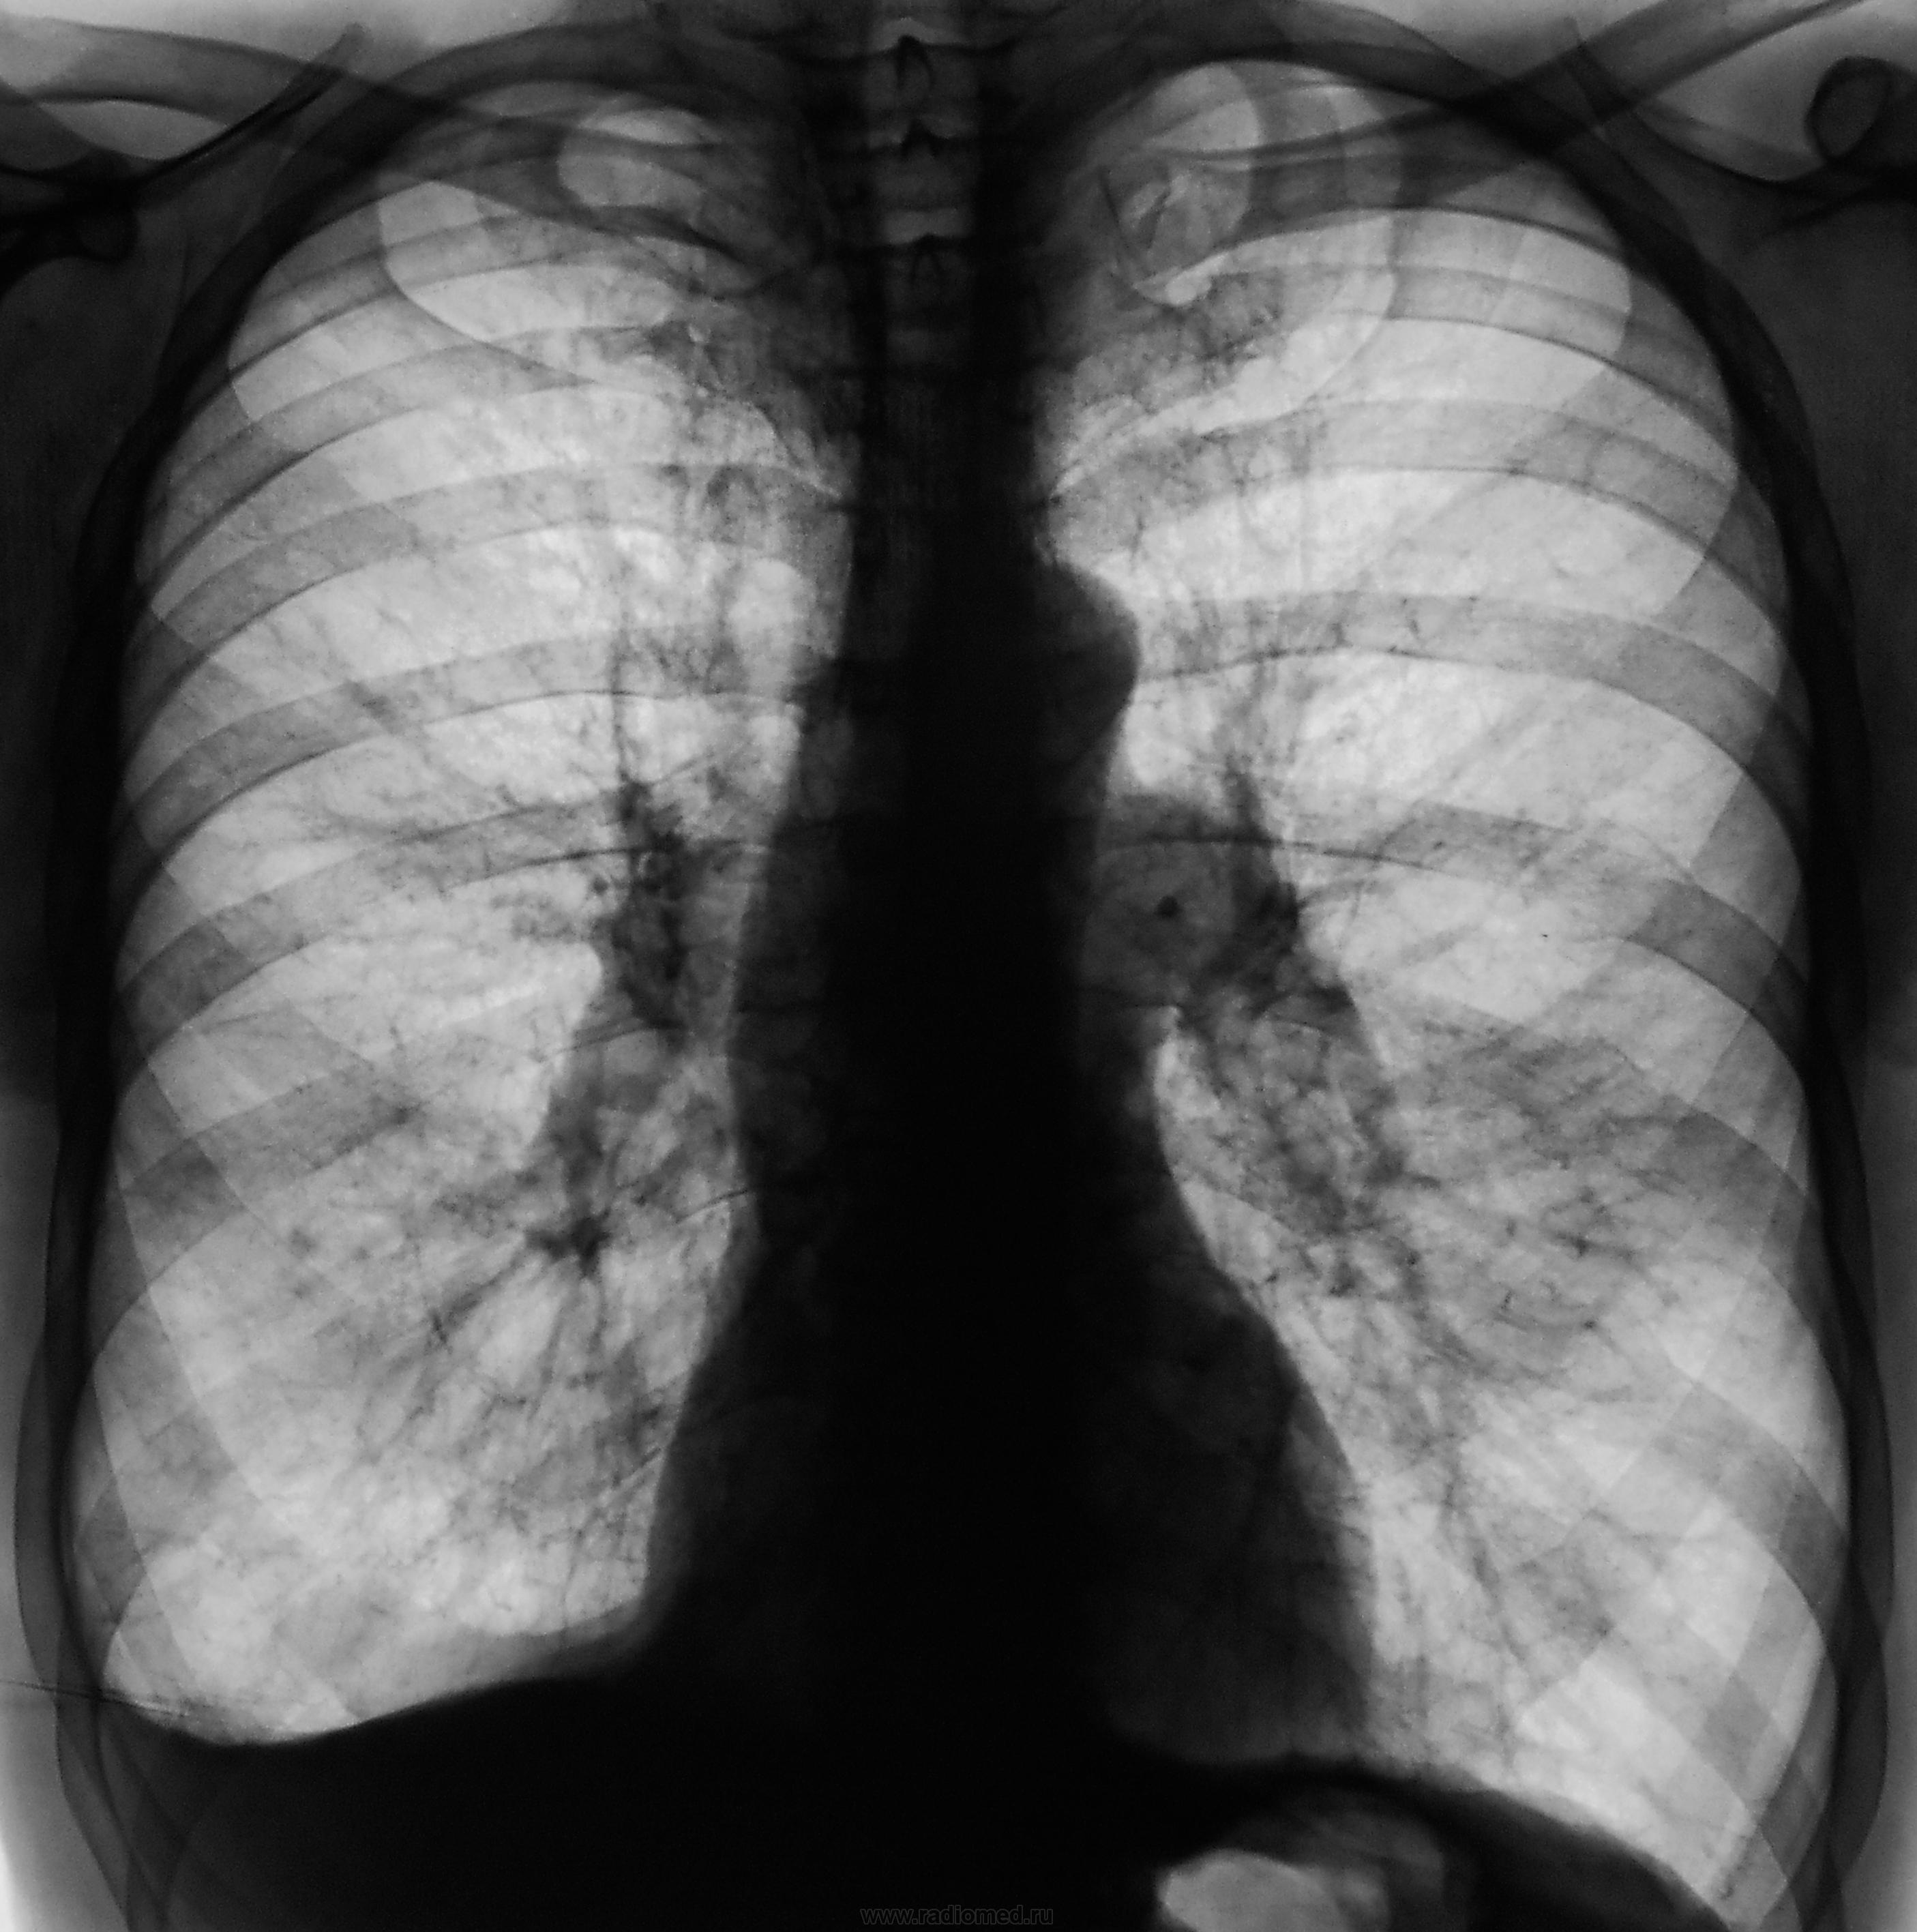

Снимок №2 - более дорзальный (предположу 9-10 см), №3 - его обработка, №4 - более вентральный срез, №5 - его обработка. Валентин Львович, отчего же Вы брезгуете указать см на снимках. S1-2 слева и S10 справа кажутся "заплеванными". Синус справа облитерирован. Корни уплотнены. Эмфизема хороша. Плевро-перикардиальные спайки слева.

На активность как-то не тянет, возможно (и скорее всего) это архивчик. Что с анамнезом и фл.архивом?

Последствия тбц.